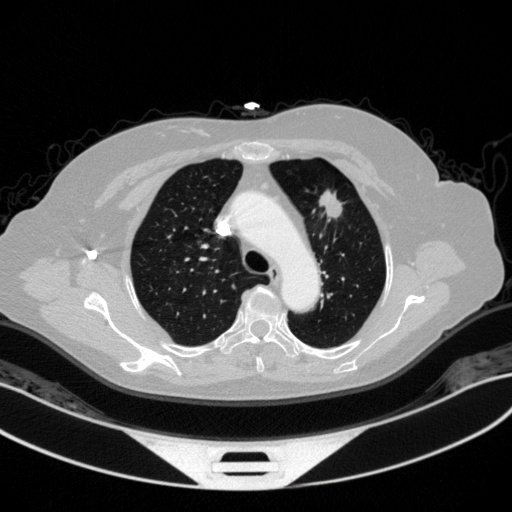

3、天池CT肺部数据集

处理好后的VOC格式的数据集图像总数为1972张,类型标签为病灶区域。